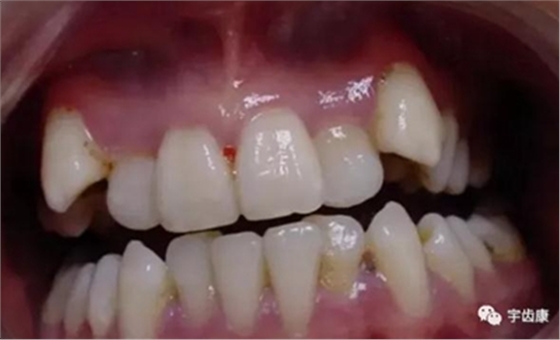

牙體解剖知識(shí)

牙體各個(gè)面的解剖厚度